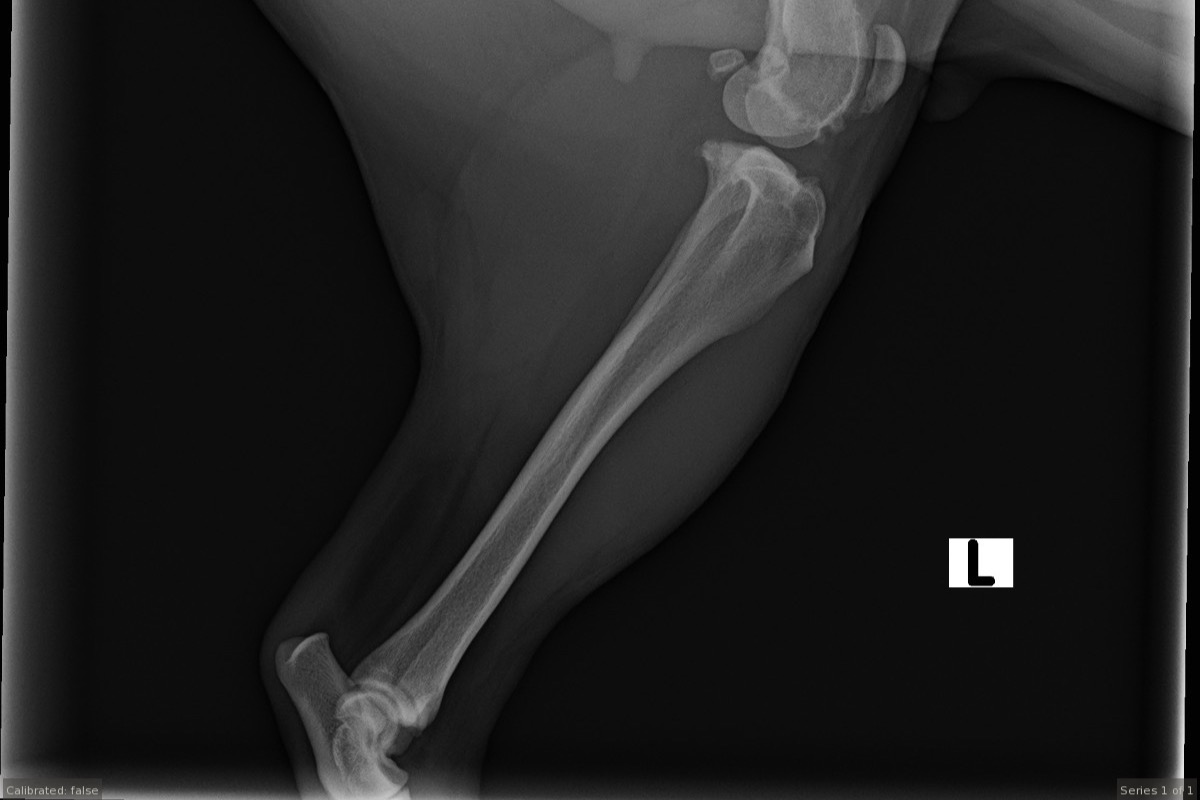

Madi had started limping here and there in July after we would go for walks or to the dog park.  It would only last a day or two then she would be back to her normal playful self.  November came and it never went away, she couldn't put any weight on her left leg.  At that point I scheduled Madi to get X-rays done in December for both hips and legs.

Two days later we found out that she has a torn ACL on her left side and a partial torn ACL on her right, hip dysplasia with subluxation, acetabular remodeling and moderate femoral neck thickening.  Her veterinarian told us she needs to have surgery on her left knee ASAP and that her right knee and both hips would probably follow soon after.